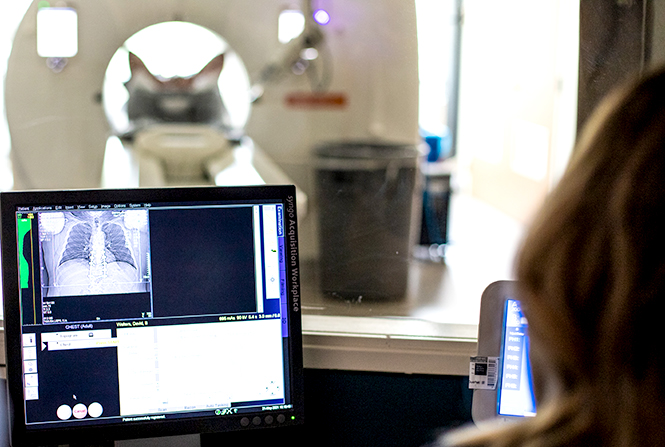

Lung Cancer Screening X Ray

Experience the clarity of Lung Cancer Screening X Ray with our curated collection of comprehensive galleries of images. featuring understated examples of photography, images, and pictures. designed to emphasize clarity and focus. Discover high-resolution Lung Cancer Screening X Ray images optimized for various applications. Suitable for various applications including web design, social media, personal projects, and digital content creation All Lung Cancer Screening X Ray images are available in high resolution with professional-grade quality, optimized for both digital and print applications, and include comprehensive metadata for easy organization and usage. Our Lung Cancer Screening X Ray gallery offers diverse visual resources to bring your ideas to life. Comprehensive tagging systems facilitate quick discovery of relevant Lung Cancer Screening X Ray content. Multiple resolution options ensure optimal performance across different platforms and applications. Time-saving browsing features help users locate ideal Lung Cancer Screening X Ray images quickly. The Lung Cancer Screening X Ray archive serves professionals, educators, and creatives across diverse industries. Instant download capabilities enable immediate access to chosen Lung Cancer Screening X Ray images. Whether for commercial projects or personal use, our Lung Cancer Screening X Ray collection delivers consistent excellence. Professional licensing options accommodate both commercial and educational usage requirements.